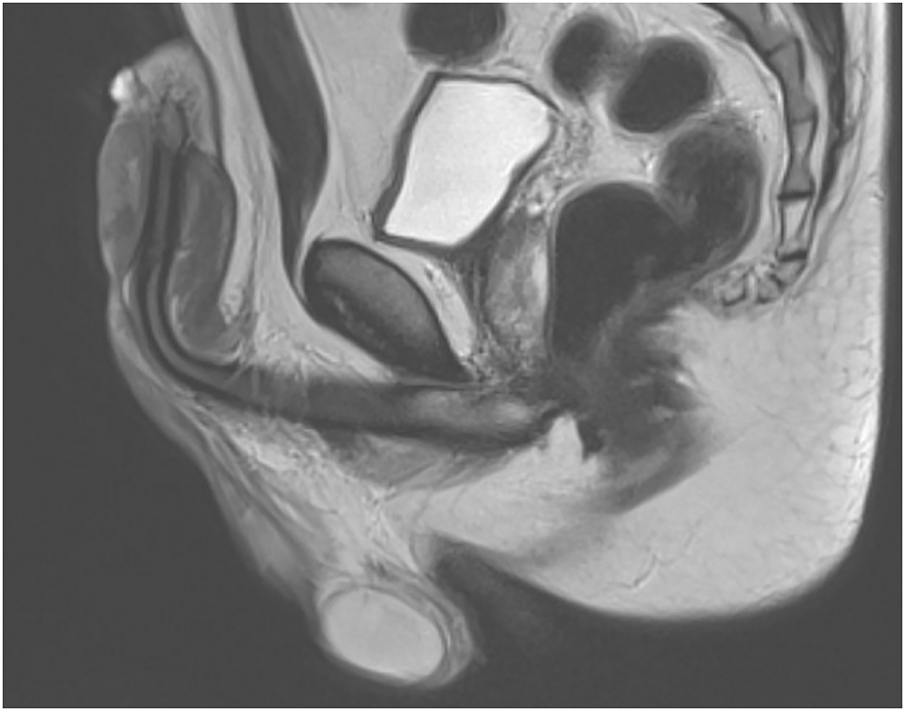

Ultrasound and MRI (Figure 2) demonstrated a diffuse thickening and infiltration of the subcutaneous tissues of the penile shaft, extending up to 1.5 cm in depth, associated with increased vascularity consistent with cellulitis.1 There was no evidence of abscess formation. The corpora cavernosa and spongiosa were unaffected. Doppler imaging demonstrated reduced vascularization of the dorsal venous plexus, likely secondary to external compression from the injected substance.

FIGURE 2. Penile MRI